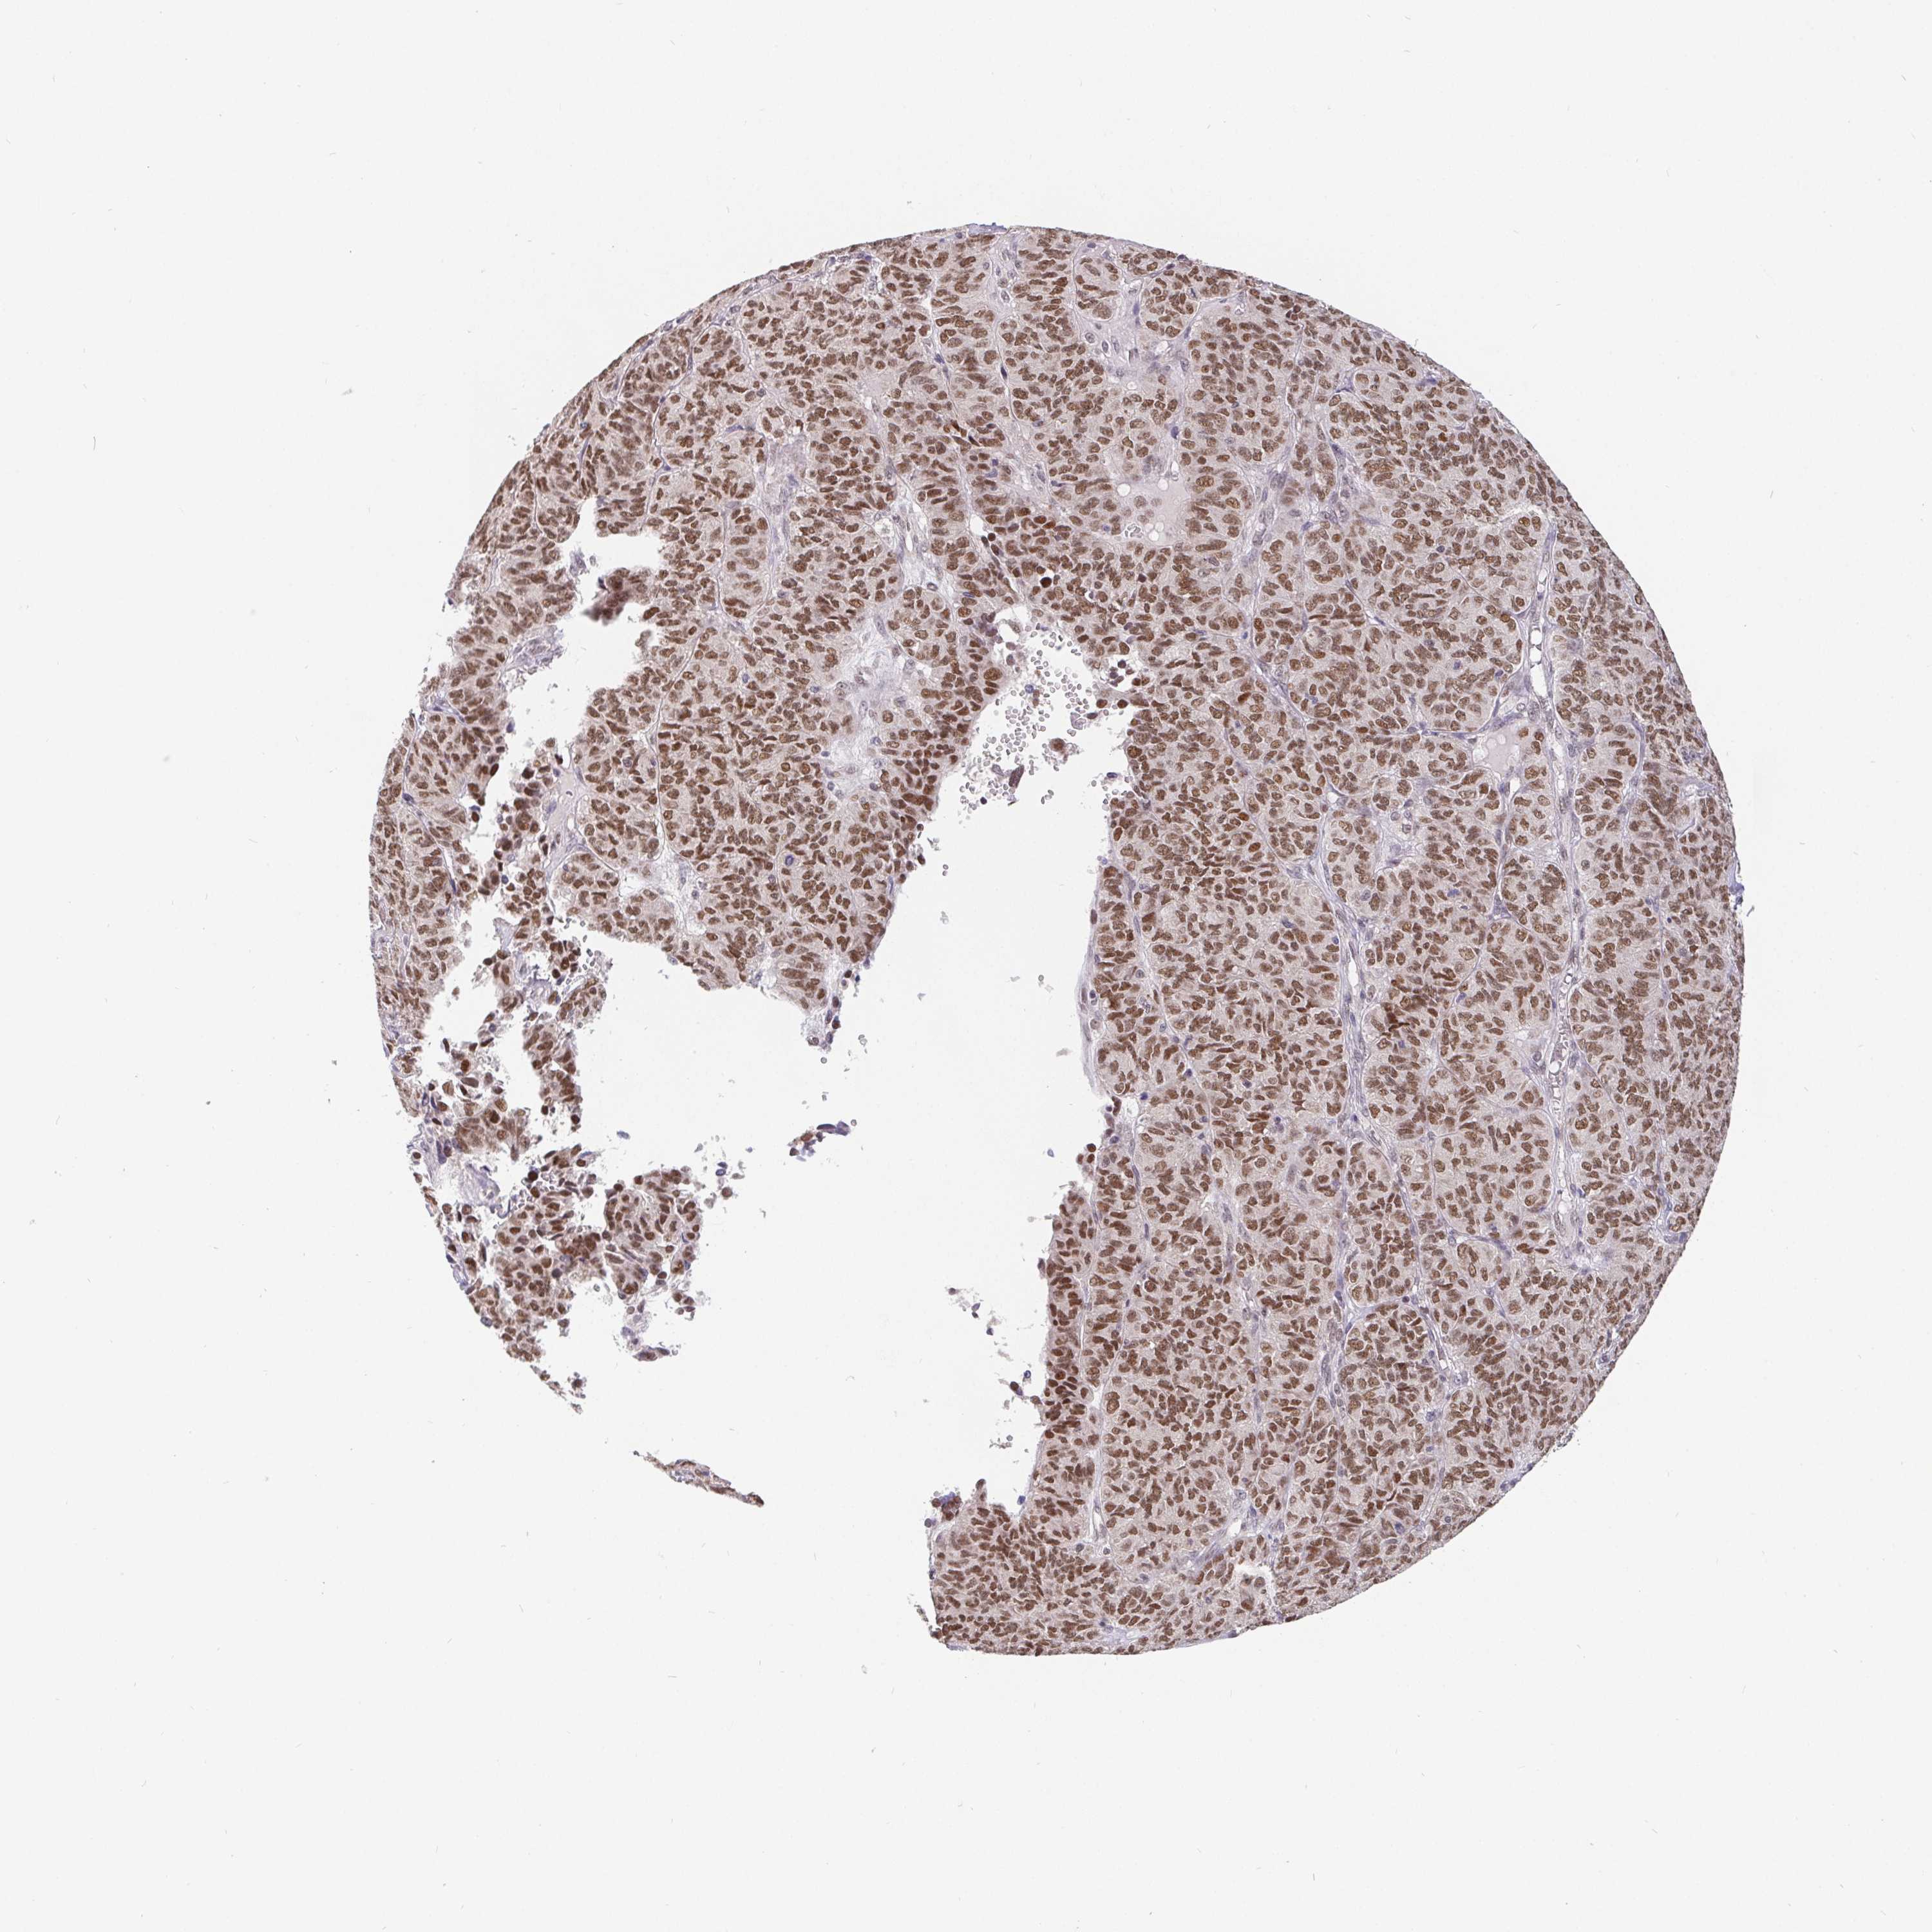

OVARIAN CANCER - Protein expressioni

A mouse-over function shows sample information and annotation data. Click on an image to view it in a full screen mode. Samples can be filtered based on level of antibody staining by selecting one or several of the following categories: high, medium, low and not detected. The assay and annotation is described here.

Note that samples used for immunohistochemistry by the Human Protein Atlas do not correspond to samples in the TCGA dataset.

Antibody stainingi

Antibody staining in the annotated cell types in the current human tissue is reported as not detected, low, medium, or high, based on conventional immunohistochemistry profiling in selected tissues. This score is based on the combination of the staining intensity and fraction of stained cells.

Each image is clickable and will lead to virtual microscopy that enables deeper exploration of all samples and also displays staining intensity scores, fraction scores and subcellular localization as well as patient and tissue information for each sample.

Antibody HPA064323

Antibody CAB002608

Staining

High

Medium

Low

Not detected

Intensity

Strong

Moderate

Weak

Negative

Quantity

>75%

75%-25%

<25%

None

Location

Nuclear

Cytoplasmic/membranous

Cytoplasmic/membranous,nuclear

Cystadenocarcinoma, serous, NOS

Cystadenocarcinoma, mucinous, NOS

Carcinoma, endometroid